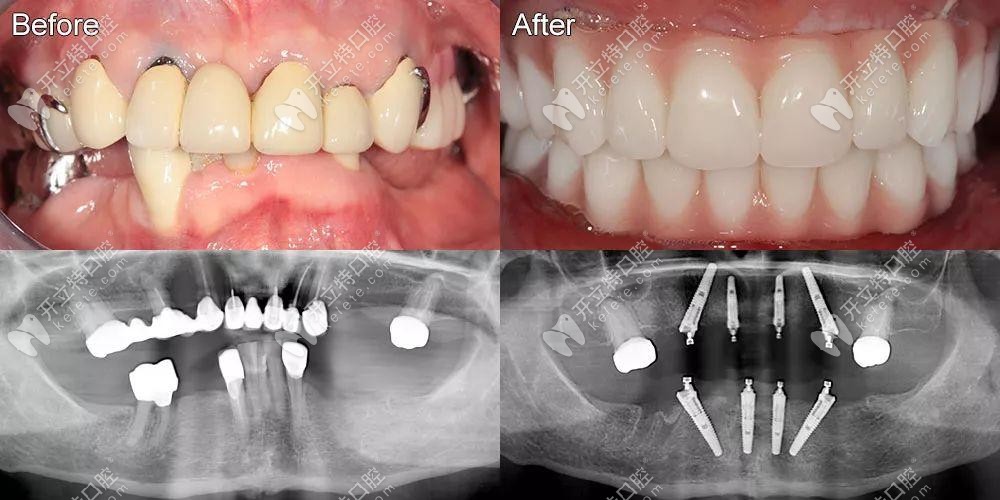

在先鋒鉆導(dǎo)板的輔助下,全口即刻負(fù)重咬合重建的病例完成了

全口種植牙即刻負(fù)重全口重建發(fā)布時(shí)間: 2025-04-18

本期主要探討利用先鋒鉆導(dǎo)板輔助定位,在優(yōu)先的自體骨條件下植入種植體并即刻負(fù)重,恢復(fù)顧客牙列缺失功能及美觀的臨床效果。